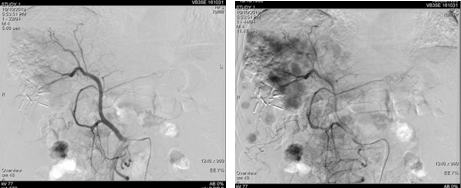

遂予肝动脉化疗栓塞(TACE)治疗,行数字减影血管造影(DSA)可见肝右叶多个结节状肿瘤染色,明确肝左、右动脉分支为肿瘤供血动脉,判定为外科术后复发。

图片

图:第一次TACE治疗

2019年2月21日以碘油5 ml+0.9%氯化钠20 ml+表阿霉素10 mg+雷替曲塞1支稀释后灌注方案行TACE治疗。后复查肝增强CT,未见明显强化,对比2019年1月病灶略缩小,初次TACE治疗达SD。